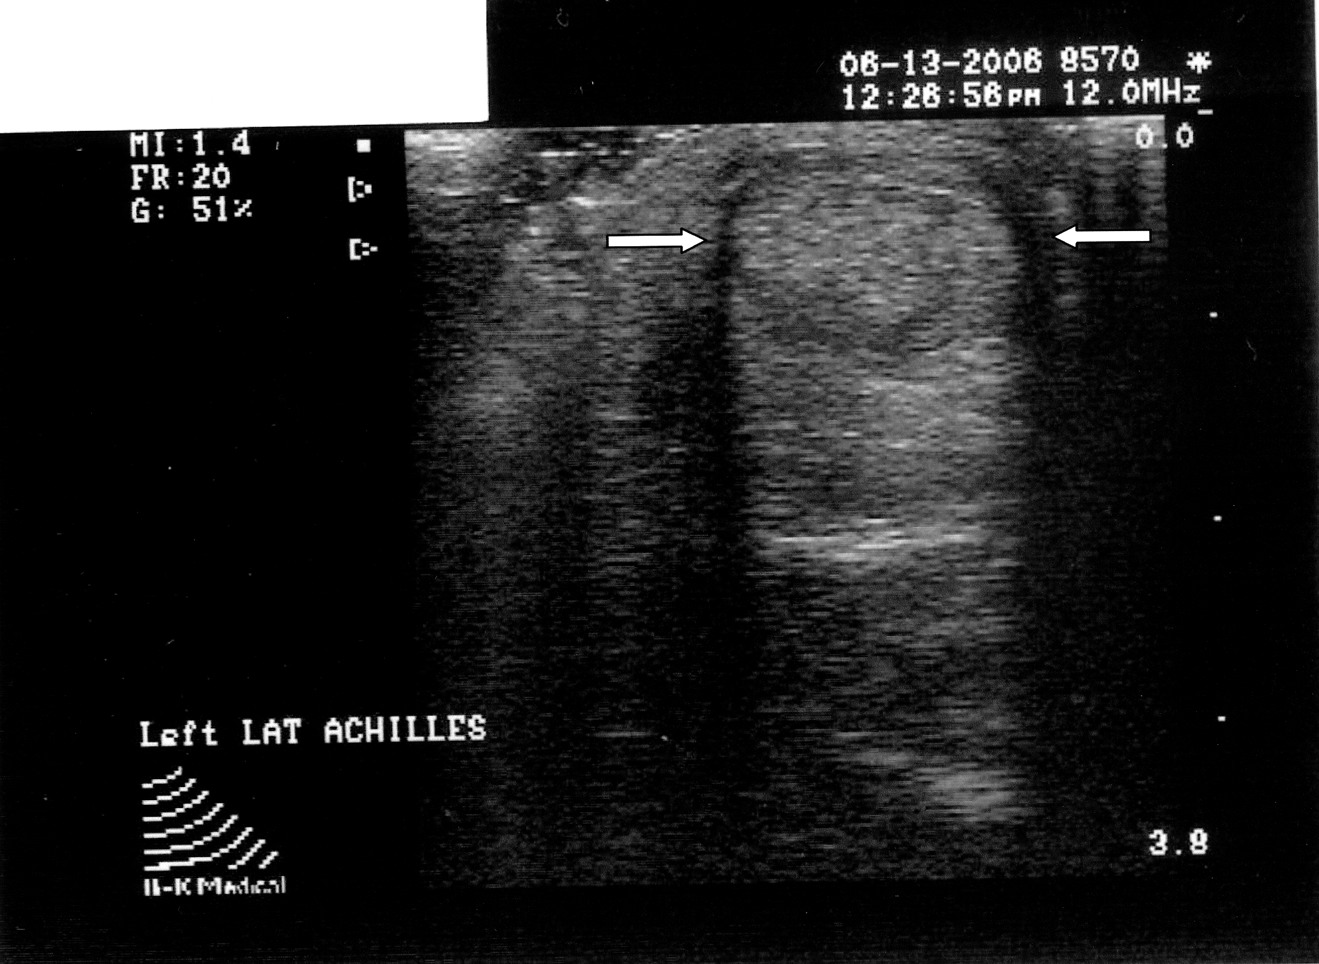

By utilizing musculoskeletal ultrasound imaging, the clinician can avoid frustration by identifying these esoteric etiologies earlier. One can also assess the severity of the problem. Indeed, clinicians can obtain quantitative measurements of the fascia and make (and document) qualitative assessments. Podiatrists can develop protocols and tailor treatment according to the severity of the condition. The more accurate assessment can help determine the success or lack thereof of the treatment plan that clinicians employ. One can scan the heel with the patient supine or prone. The preferred method is to have the patient in the prone position. Most clinicians lean toward this position because it tends to be easier for the examiner. Assess all three bands: medial, central and lateral. The examiner can scan in the long axis (sagittal plane) and the short axis (coronal plane). By far, the long axis will give the best information on the status of the fascia. One should assess the quality of the fascia. A normal fascia will have a fibrillar pattern. There will be anisotropy present where the fibers attach to the inferior aspect of the calcaneus. Take care not to confuse this with pathology. When documenting this properly, it is important to include a photo with the written description. Assessment then proceeds with measurement of the plantar fascia. Measure at the inferior aspect of the heel. Place the digital calipers at the hyperechoic line that represents the inferior aspect of the heel and the hyperechoic outline of the fascia at its most plantar expansion. (Just to clarify, the superior aspect of the image on the screen represents the plantar aspect of the heel. In other words, the image is inverted. By U.S. convention, the right of the screen should represent distal and the left of the screen would be proximal. Turning the probe 180 degrees will correct the orientation if one finds this not to be the case.) A fascial thickness of 4 mm has been mentioned as the upper limit of normal. When it comes to fascial thickness, I have even heard that one should consider upper normal limits of 4 mm for the medial band, 3 mm for the central band and 2 mm for the lateral band. Barrett, et. al., have looked at cadavers and plantar fascial thickness.1 It stands to reason that fascial thickness will vary depending on the size of the individual. I have seen this in my own practice. I have measured a patient’s normal fascia at 5 mm in thickness numerous times. Accordingly, when it comes to a unilateral case, one must compare the affected heel to the contralateral side. Another pitfall to avoid is including the deep musculature (i.e. flexor digitorum brevis) in one’s measurement. In some individuals, the muscular layer can be delineated deep to the fascia at the heel. Documentation of an ultrasound of the heel can be in a separate report or as a subset of the objective part of one’s notes. Either way, photos should accompany the written report. The assessment should include the measurements of all three bands of the symptomatic fascia and, in a unilateral case, the asymptomatic heel as a comparison. Along with the quantitative assessment, one should include a qualitative description as well and utilize proper terminology. Here are some of the more common terms: • Hyperechoic: increased echo or brightness on the screen • Hypoechoic: decreased echo or gray to dark on the screen • Anechoic: lack of echo or black on the screen • Fibrillar pattern: normal fiber pattern of tendon or ligament • Echotexture: general term referring to the internal architecture of the structure and the echo pattern seen